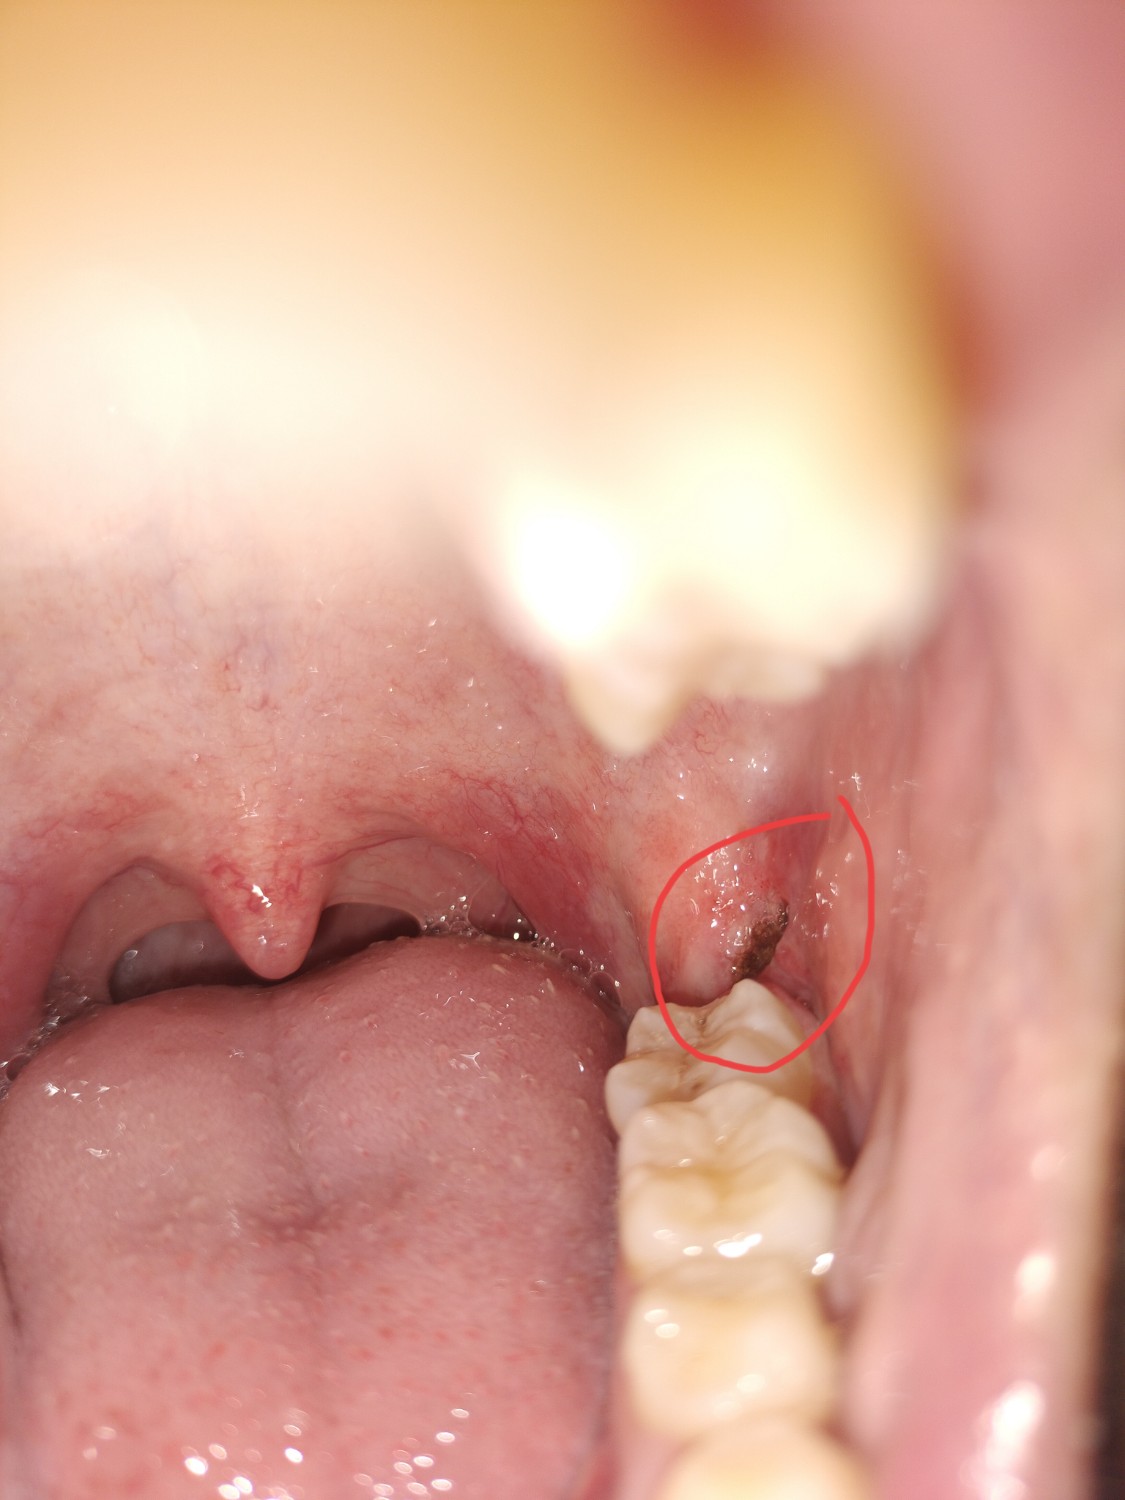

พอดีไปผ่าฟันคุดมาคับแล้วเมื่อวานตัดไหมไป แล้ววันนี้ส่องดูที่แผลเห็นมีก้อนสีน้ำตาลตรงรูแผล มันคืออะไรครับ

ผ่านมา 4 วัน ต้องคาฟันไม่ให้วางทับกัน วันนี้ต้องวางสูงขึ้นกว่าวันอื่น ๆ ไม่รู้ว่าเพราะบวมขึ้นไหม // แผลดูปกติไหมคะ ที่วงกลมนั่นคืออะไร เพิ่งขึ้นมาวันนี้เลยค่ะ 🥹

พอดีแผลตรงที่ผ่ามันยังไม่ปิดสนิทหมอตัดไหมให้แล้ว แต่ว่ามันมีอะไรดำๆข้างในไม่รู้คะ เป็็นเศษอาหารหรือคราบเลือดทั่วไปหรอคะ เป็นก้อนดำๆอยู่ข้างในแผลทั้งแผลเลย